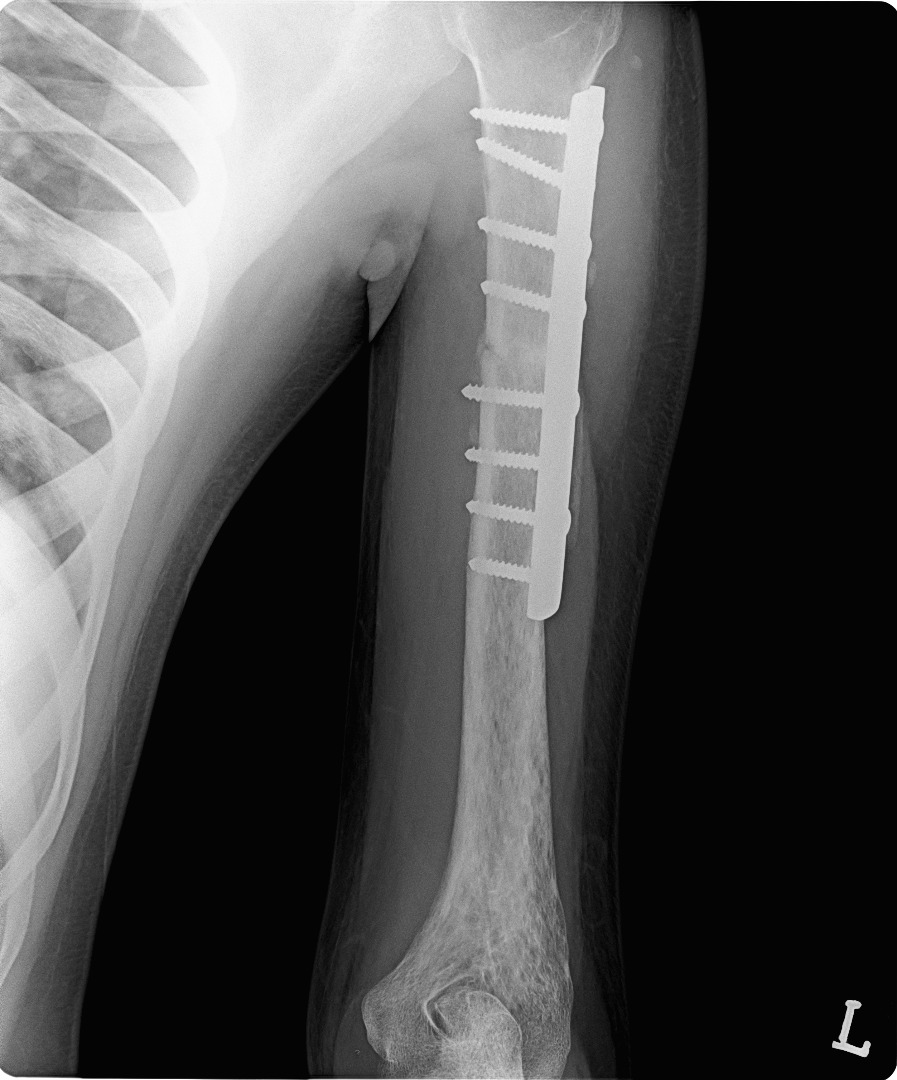

TRAUMA SURGERY & MINIMALLY INVASIVE FRACTURE SURGERY

trauma surgery

minimally invasive fracture surgery